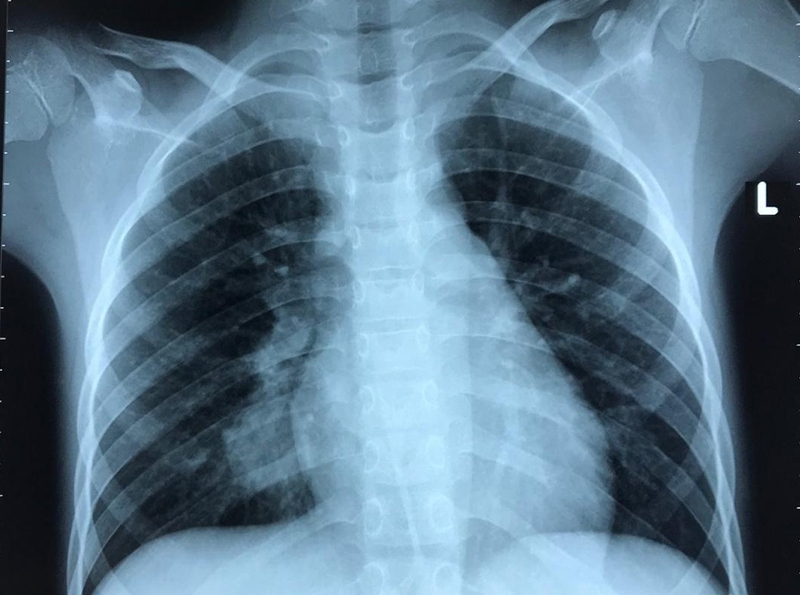

Khám cận lâm sàng: